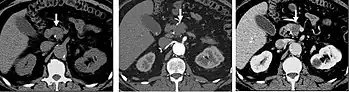

Kidney masses

Detection and characterization of renal parenchymal masses is a frequent indication for CT. An initial noncontrast CT is important for detecting calcium or fat in a lesion, and to provide baseline attenuation of any renal masses. Following noncontrast scanning, intravenous contrast is injected and a corticomedullary phase is obtained at approximately 70 seconds (figure 7a, 7b). The corticomedullary phase is characterized by enhancement of the renal cortex as well as the renal vasculature. This phase is valuable in the evaluation of benign renal variants, lymphadenopathy and vasculature, however certain medullary renal masses may not be visible during this phase due to minimal enhancement of the medulla and collecting system. The parenchymal phase is obtained approximately 100–200 seconds after the injection of contrast material (figure 7c). Parenchymal phase imaging demonstrates continued enhancement of the cortex, enhancement of the medulla, and various levels of contrast material in the collecting system. The parenchymal phase is highly important for the detection and characterization of renal masses, parenchymal abnormalities, and the renal collecting system. This method of imaging does not evaluate for abnormalities of the collecting system.

Common renal masses can occasionally be differentiated from each other using this imaging technique. Renal cell carcinomas and oncocytomas typically demonstrate intense heterogeneous enhancement on the parenchymal phase images and cannot be reliably differentiated from each other but can be distinguished from other renal masses. Angiomyolipomas (AML's) also demonstrate intense contrast enhancement but characteristically contain macroscopic fat which can be detected on the noncontrast images, and can help to differentiate AML's from renal cell carcinomas and oncocytomas. Renal lymphoma on the other hand, will often have decreased enhancement when compared to the renal parenchyma on the parenchymal phase images.

FIGURE 7. Selected images from a renal mass specific protocol CT. Corticomedullary phase (axial 7a) demonstrates peripheral enhancement of the renal cortex with minimal opacification of the renal medulla. There is a large renal cell carcinoma in the left kidney (right in image) which can be differentiated from the normal renal parenchyma by the heterogeneous and differential enhancement. The renal artery and vein are opacified in this phase as well. The collecting system is not opacified (coronal reformat 7b). In the parenchymal phase, the renal cortex and the medulla are enhancing. The renal cell carcinoma in the left kidney is not as well defined when compared to the corticomedullary phase images, but is actually slightly more conspicuous. There is some contrast noted within the collecting system during this phase (7c).